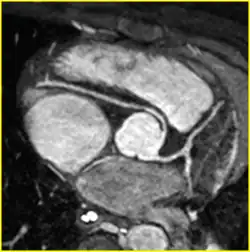

| Anomalous origin of the right coronary artery from the left coronary sinus on MRI with an inter-arterial, potentially dangerous course. | |

Anomalous aortic origin of a coronary artery (AAOCA) is a rare congenital heart defect in which a coronary artery inappropriately arises from the aorta, usually from the incorrect sinus of Valsalva. This anomalous coronary artery often takes an interarterial (between the aorta and pulmonary artery), intraconal (within the myocardium), or intramural course (within the aortic wall), and is associated with an increased risk of sudden death in children.